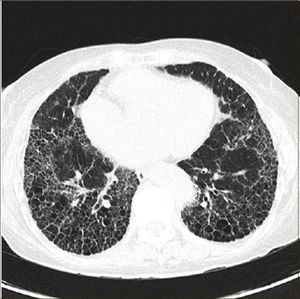

Además exige el patrón radiológico característico de UIP en tomografía axial computarizada de tórax de alta resolución, cuando los pacientes no son sometidos a biopsia quirúrgica pulmonar. Este patrón se expresa con opacidades reticulares a menudo asociadas con bronquiectasias por tracción y con panal de abejas, elemento crítico para hacer el diagnóstico, con distribución basal y periférica y también en parches. El panal de abejas lo constituyen agrupaciones de espacios aéreos quísticos de diámetros comparables de 3-10 mm (ocasionalmente hasta 2.5 cm), subpleurales, con paredes definidas (Figura 1). Puede haber vidrio esmerilado, pero de extensión menor que el reticulado. Adenopatías mediastínicas pueden aparecer, en general menores de 1.5 cm.

Las alteraciones pleurales, los micronódulos, el atrapamiento aéreo, quistes no de panal, extenso vidrio esmerilado, consolidaciones, distribución peribroncovascular son todas alteraciones que sugieren fuertemente un diagnóstico alternativo (Tabla 1).